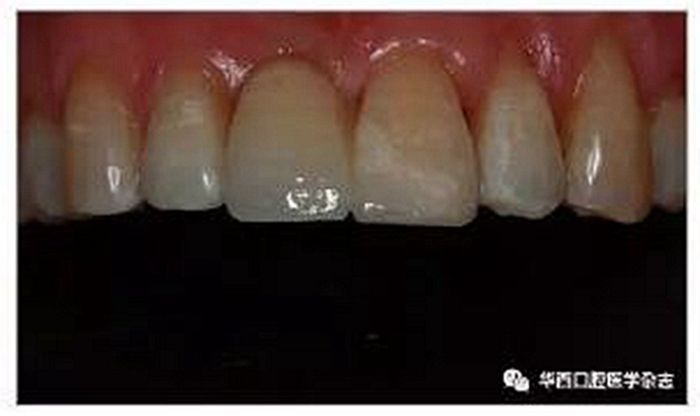

本研究選擇3M公司的RelyXTM Ultimate clicker 樹脂水門汀粘接套裝進行粘接。1)基牙的處理:患牙上橡皮障后,常規(guī)00號排齦線排齦,37%磷酸凝膠酸蝕粘接面30 s,水霧徹底沖洗60 s,吹干,酸蝕后的釉質(zhì)粘接面呈白堊色,用小毛刷在表面涂一薄層通用型樹脂粘接劑,氣槍輕吹,使得其在粘接面形成一層均勻一致的光亮薄膜。2)修復體的處理:采用9.5%氫氟酸酸蝕修復體粘接面20 s,氣槍水霧沖洗,而后置于SW1500型超聲清洗機(日本西鐵城電子株式會社)中,在95%乙醇中超聲清洗3 min,以徹底去除修復體組織面酸蝕后的雜質(zhì),吹干,于粘接面表面涂布一薄層通用型樹脂粘接劑,氣槍輕吹,使其在粘接面形成一層均勻一致的光亮薄膜;然后于修復體粘接面涂布雙固化型樹脂水門汀,將修復體就位,小毛刷清理牙齦緣溢出的多余樹脂水門汀,光固化燈初步光照3 s,用牙線迅速清理鄰間隙處多余的樹脂水門汀后,用光固化燈各個方向光照20 s,使樹脂徹底固化;粘接后進行正中、前伸及側(cè)方的咬合調(diào)整,確保橋體除在正中咬合時保持輕接觸外,在前伸、側(cè)方咬合時均不接觸[3,7];最后用拋光車針精修修復體邊緣并拋光(圖4)。

圖4 修復完成后影像